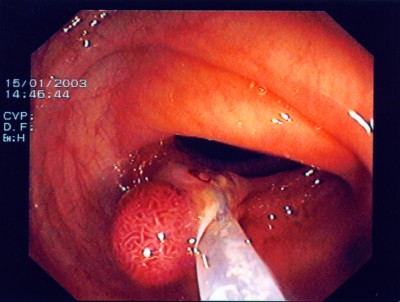

Großer Polyp des Dickdarmes